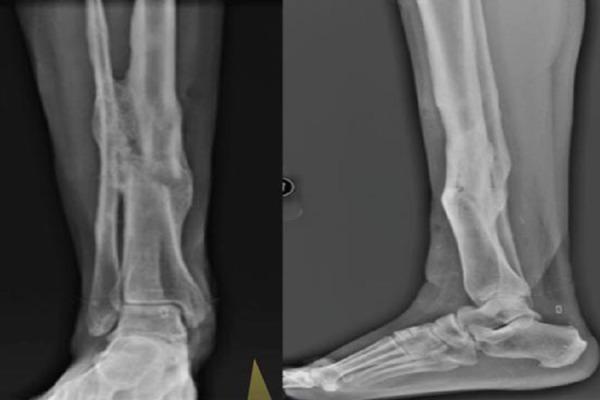

Compound distal tibia fractures have high incidence of nonunions and have varied presentation as far as status of fibula is concerned. If fibula is sufficiently healthy we can use it for bridging the nonunion of tibia.

We present a case of 20 year old female with compound and segmental tibia fracture. Primary stablisation by external fixation and later cast brace application achieved union at the proximal end of the segmental fragment with non union at the distal end. This was then treated with bridge grafting of fibula and screw fixation of fibula to the tibia. Five years follow shows good clinical and functional outcome without any complications.

Its infrequent to find fibula spanning across the tibia nonunion, however when available this can be used as bridge graft to promote healing.